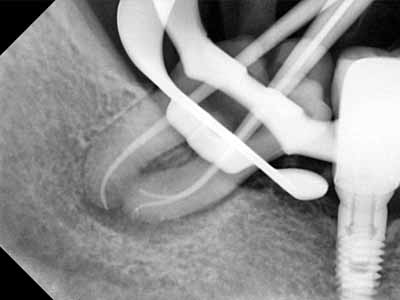

Frontier in Micro Dentistry and Endodontics

drg. Dennis,MDSc.,Sp.KG, Subsp. KE(K)., Ph.D

Dokter Gigi Spesialis Konservasi Gigi Konsultan, Master of Dental Science